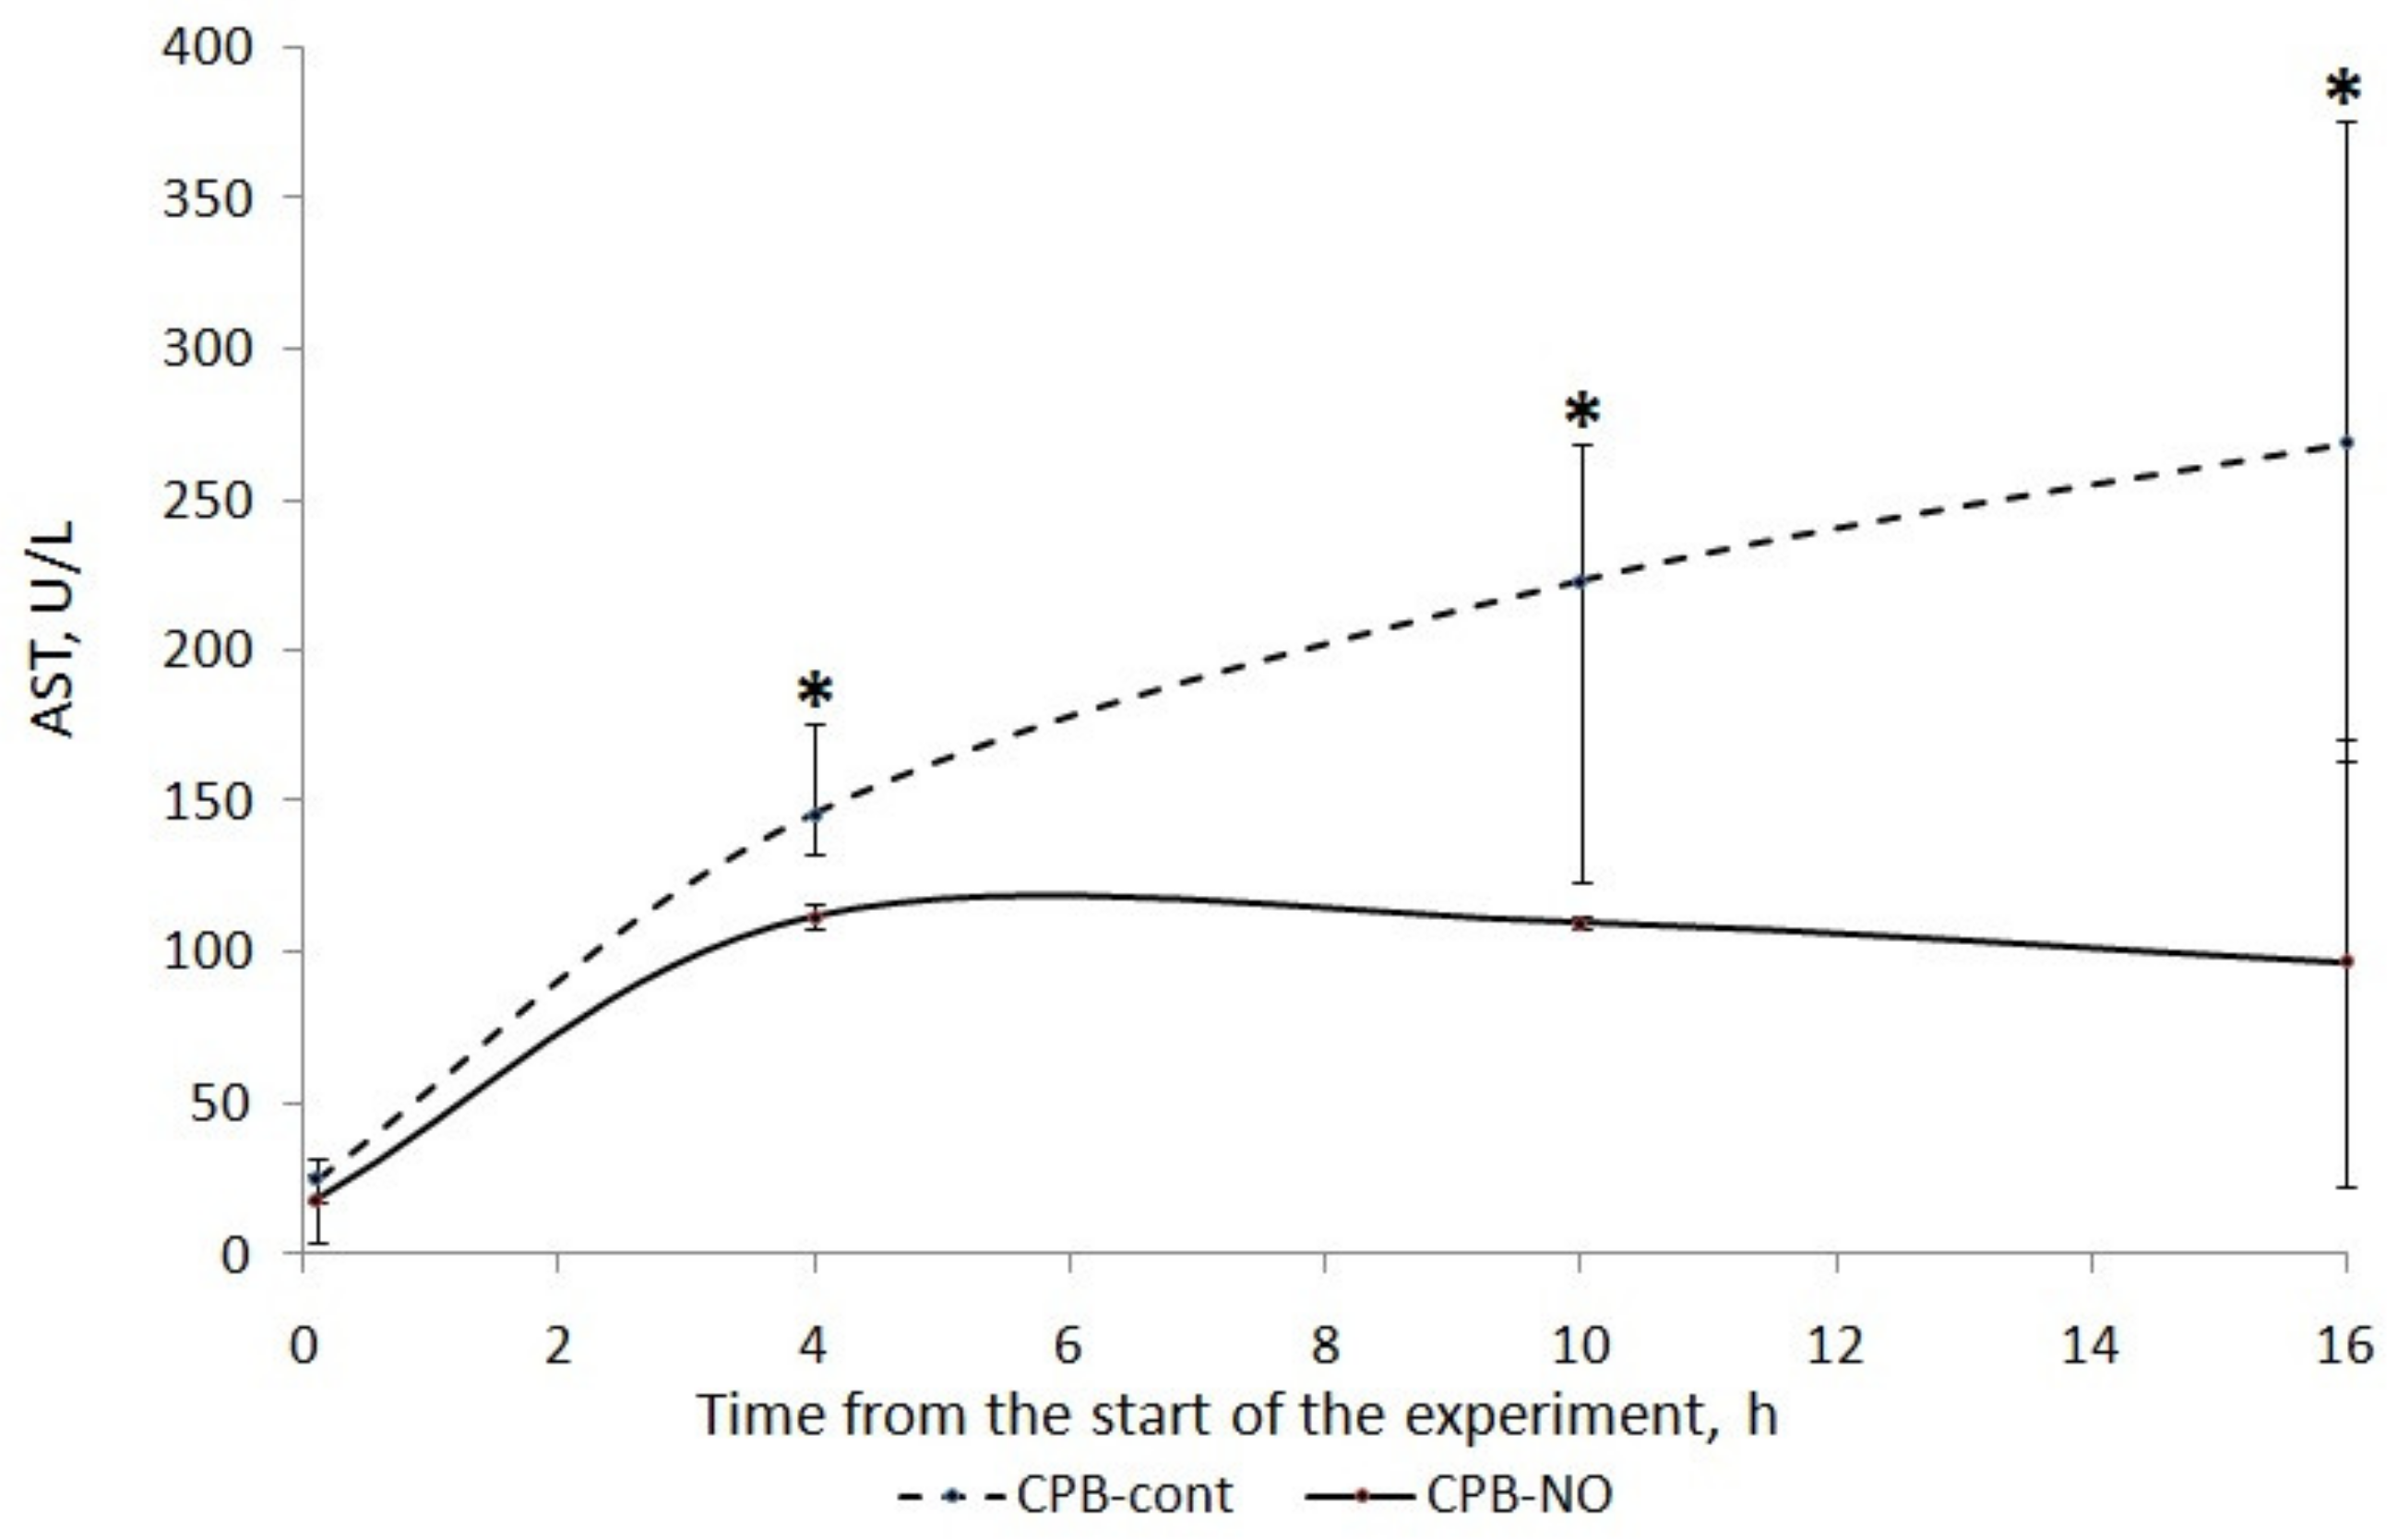

3.1. Assessment of Liver Function

| Point | CPB-contr, n = 5 | CPB-NO, n = 5 | Mann–Whitney U-Test |

|---|---|---|---|

| Baseline (1) | 25 (17; 26) | 18 (16; 32) | p = 0.91 |

| Weaning CPB (2) | 146 (129; 174) | 112 (99; 116) | p = 0.421 |

| 6 h after CPB (3) | 223 (124; 269) | 110 (99; 112) | p = 0.175 |

| 12 h after CPB (4) | 269 (164; 376) | 97 (94; 171) | p = 0.175 |

| Wilcoxon test | p1–2 = 0.043 p1–3 = 0.043 p1–4 = 0.043 | p1–2 = 0.043 p1–3 = 0.068 p1–4 = 0.08 | |

| AUC AST (U/L/16 h) | 2325 (1255; 2669) | 1094 (1013; 1248) | p = 0.117 |

| Max. AST (U/L) | 269 (174; 376) | 112 (111; 283) | p = 0.076 |